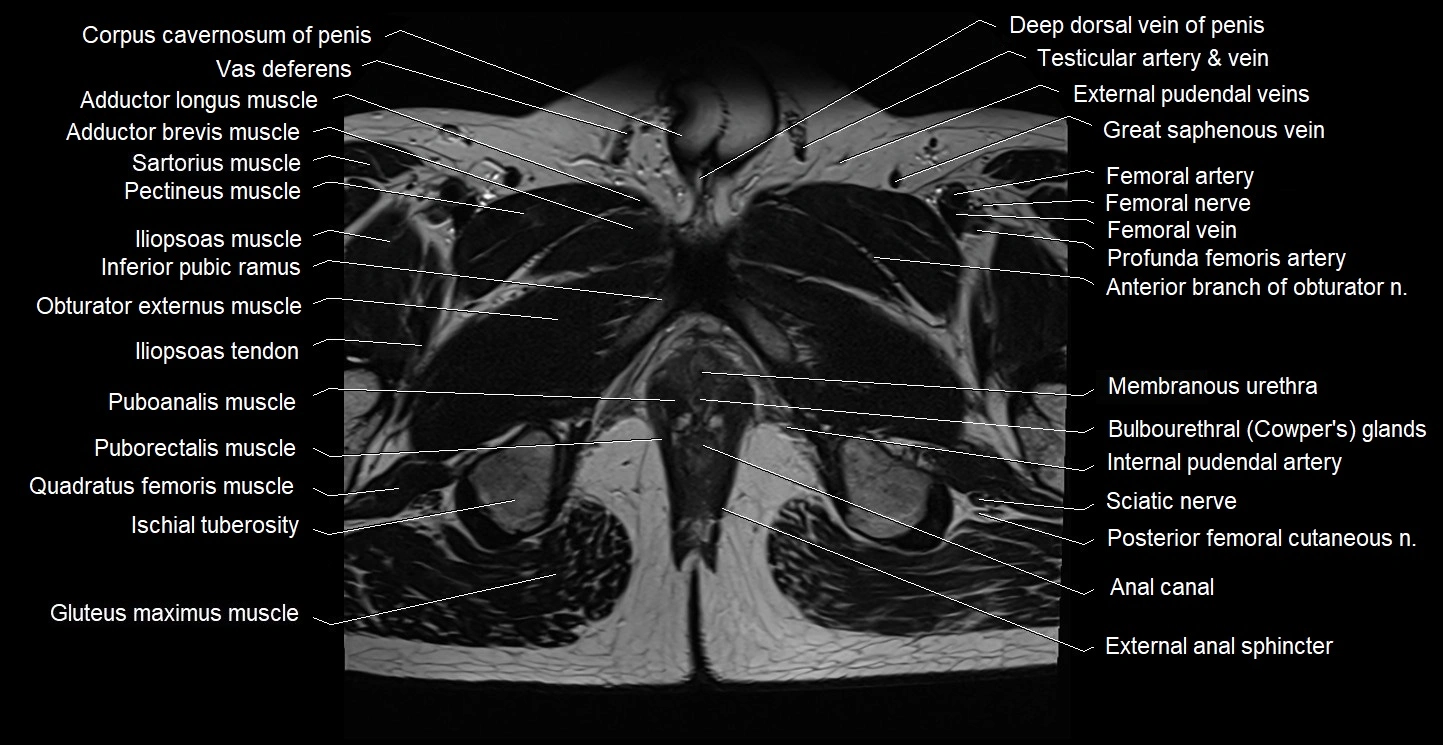

- Adductor brevis muscle

- Adductor longus muscle

- Anal canal

- Bulbourethral gland (Cowper’s glands)

- Corpus cavernosum

- Deep femoral artery (profunda femoris)

- External anal sphincter

- Femoral artery

- Femoral nerve

- Femoral vein

- Gluteus maximus muscle

- Iliopsoas muscle

- Iliopsoas tendon

- Inferior pubic ramus

- Internal pudendal artery

- Ischial tuberosity

- Membranous urethra

- Obturator externus muscle

- Pectineus muscle

- Posterior femoral cutaneous nerve

- Puboanalis muscle

- Puborectalis muscle

- Quadratus femoris muscle

- Sciatic nerve